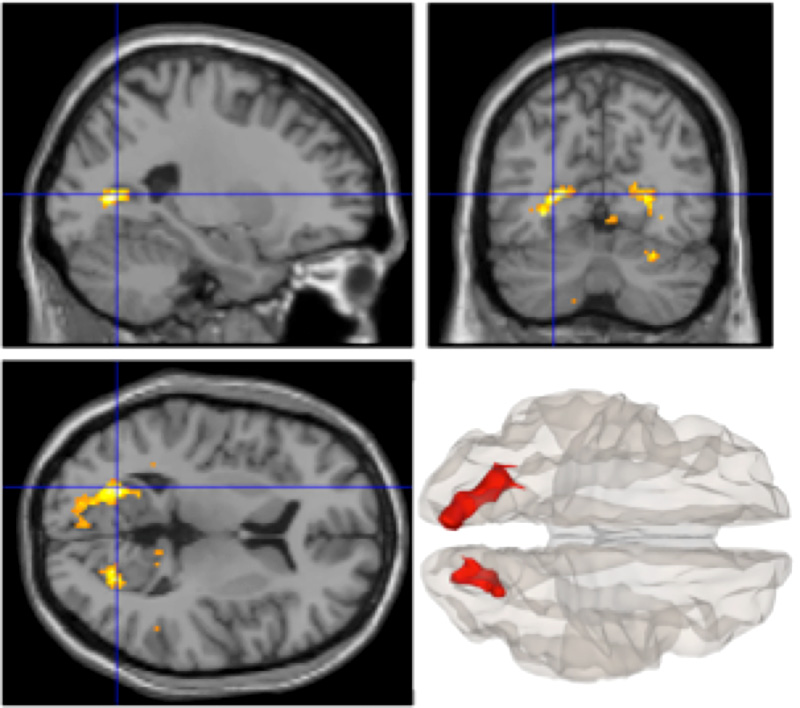

本研究グループは、瞑想実践者の洞察瞑想時の脳活動をMRI装置で測定し、脳領域間の関係を調べる機能的結合性解析を実施しました。その結果、洞察瞑想時に、自分の過去の経験に関する記憶に捉われる程度と関係していると考えられる、腹側線条体と脳梁膨大後部皮質の結合性が低下することを発見しました。この結果は、今この瞬間に生じている経験に「ありのままに気づく」際に、自分の過去の経験に関する記憶に捉われる程度が低下していることを示唆しています。今後は、洞察瞑想によって自分の過去の経験から自由になれるという観点から、マインドフルネス実践法が日々の健康や幸福感を高めるメカニズムを解明することが期待されます。

図:集中瞑想時と比較して、安静時から洞察瞑想時にかけて、左腹側線状態との結合性が低下した脳梁膨大後部皮質を中心とした脳領域を示している。